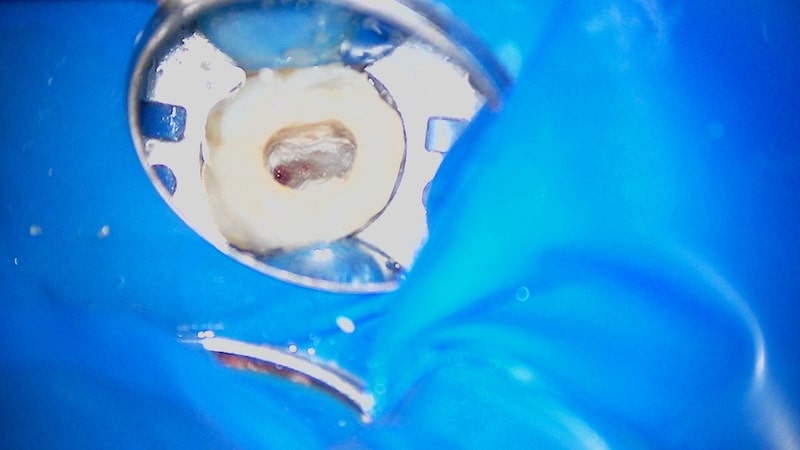

症例9 大臼歯 生活歯髄治療

術前

CT

術前実写

術中

治療1

治療2

術後